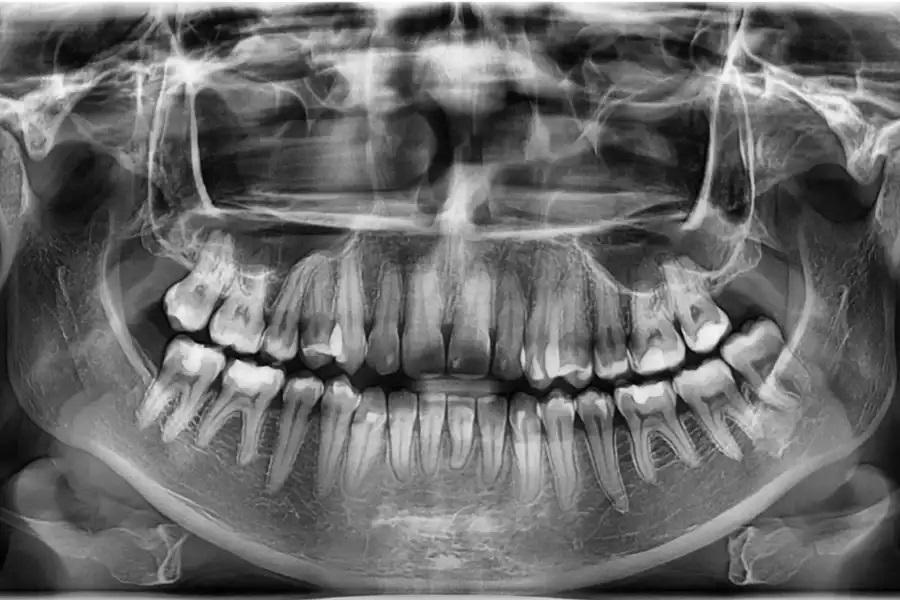

Рентгенологическое наблюдение

Повторная оценка по данным панорамной рентгенографии и цефалометрии используется для подтверждения интрузии боковых зубов без резорбции корней или изменений в области пазух, улучшения наклона верхних резцов в пределах костной ткани, изменений профиля губ, соответствующих авторотации пр. ч. с., и благоприятных скелетных параметров. (фото 17 – 20)

Фото 17. Панорамная рентгенограмма до лечения. Базовое изображение, демонстрирующее исходные дентоальвеолярные взаимоотношения. В области премоляров и моляров отмечается нормальный уровень краевой кости и прикрепления, служащий ориентиром для последующего сравнения.

Фото 18. Панорамная рентгенограмма через 15 месяцев после завершения лечения. Выявлено выраженное двустороннее дентоальвеолярное ремоделирование в области премоляров и моляров. Альвеолярный отросток вместе с зубами смещен краниально, что соответствует успешной интрузии боковых зубов и авторотации нижней челюсти пр. ч. с. Уровень краевой кости и прикрепления остался неизменным, признаков резорбции корней или изменений в области пазух не выявлено, что свидетельствует о стабильной костной адаптации и сохранности пародонта.